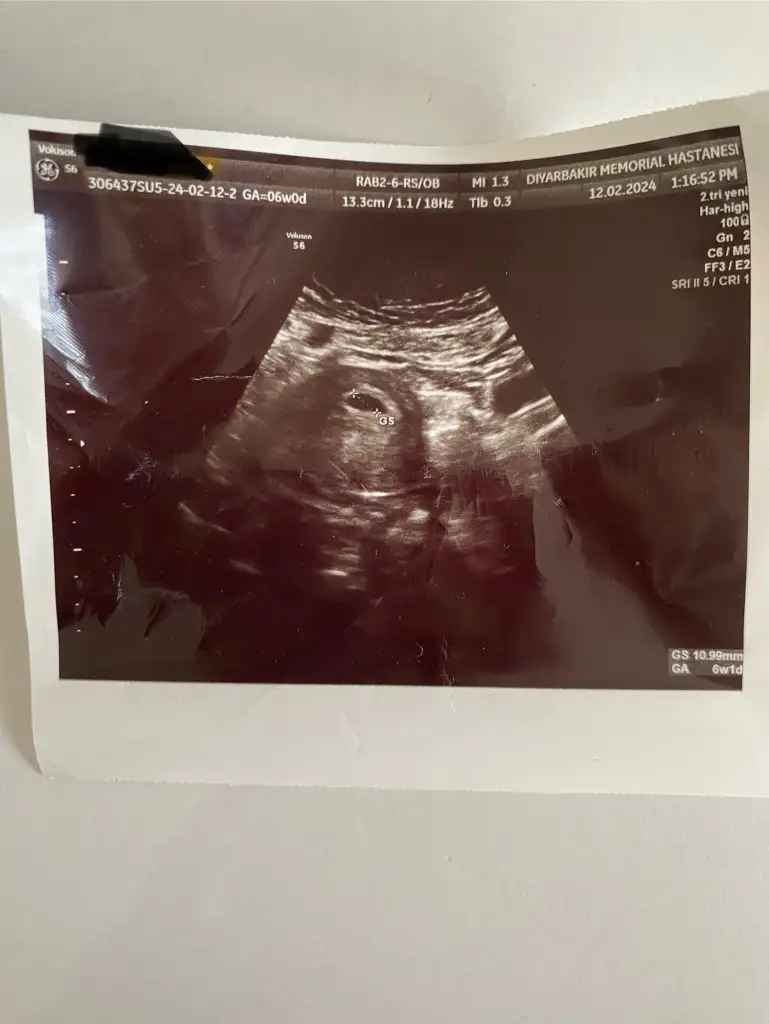

Canım karından bakıldı galiba dimi ondan görülmemiştir bebek haftaya görürsün benceArkadaşlar keseden anlayan varmı yada yazılardan falan doktorum sadece kese var güzel demişti haftaya kalp atışı için gel dedi bende hiç bişey sormadan eve geldim her doktora gitiğimde söyliyeceklerim alkımdam uçup gidiyor sanki 6 hfata denildi bende keseye baktım içinde hiç bebek yok

Valla benim keseyle karşılaştırıp yorumlamaya çalıştım ama olmadı.Bence her şey yolunda çünkü doktor başta bebeği görmedi sonra kalp atışını duyabiliriz dedi. Bana aynen şöyle söyledi kalp atışını duyduk ama duymasaydik bile gayet sağlıklı derdim dedi. Bence bı kaç güne bebek görünür.Arkadaşlar keseden anlayan varmı yada yazılardan falan doktorum sadece kese var güzel demişti haftaya kalp atışı için gel dedi bende hiç bişey sormadan eve geldim her doktora gitiğimde söyliyeceklerim alkımdam uçup gidiyor sanki 6 hfata denildi bende keseye baktım içinde hiç bebek yok

Canım 6 hafta olduğundan emin misinArkadaşlar keseden anlayan varmı yada yazılardan falan doktorum sadece kese var güzel demişti haftaya kalp atışı için gel dedi bende hiç bişey sormadan eve geldim her doktora gitiğimde söyliyeceklerim alkımdam uçup gidiyor sanki 6 hfata denildi bende keseye baktım içinde hiç bebek yok

Bir de her doktorun ultrason cihazı aynı değil ilk gittiğim tüp bebek merkezi ve o kadar net ki her şey sonra gittiğim zar zor gördü bendeArkadaşlar keseden anlayan varmı yada yazılardan falan doktorum sadece kese var güzel demişti haftaya kalp atışı için gel dedi bende hiç bişey sormadan eve geldim her doktora gitiğimde söyliyeceklerim alkımdam uçup gidiyor sanki 6 hfata denildi bende keseye baktım içinde hiç bebek yok